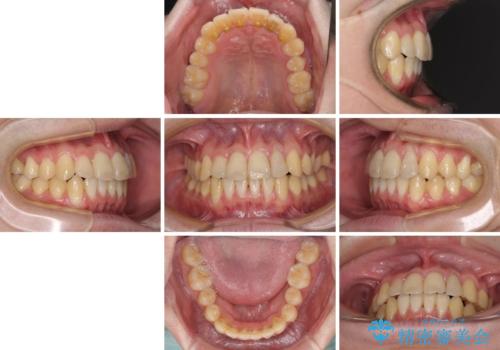

前歯のクロスバイト インビザラインによる矯正治療

- 上下のクロスバイトと前歯のデコボコを気にして来院された患者様です。

インビザラインを用い、IPR(歯と歯の間を削る)と歯列全体を拡大させることで、歯並びを整えていくこととしました。

上下ともに歯列全体を後方に移動させるため、上下の親知らずを抜歯することとしました。

奥に位置していた上の前歯が下の前歯を乗り越える際、奥歯でものを咬むことができず、辛い時期が続きました。